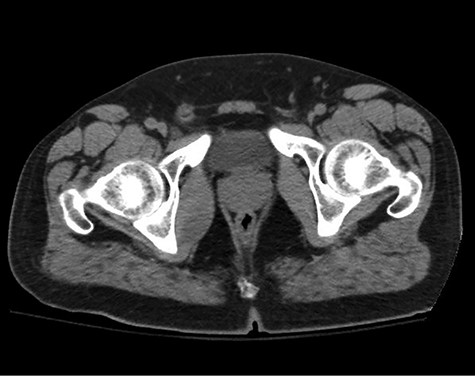

A healthy 47-year-old male with past medical history significant only for hypertension and nephrolithiasis presented to Englewood Health Medical Center in October 2019 with right flank pain radiating to the pubis, hematuria, hard stool with straining and fifteen pound weight loss over 6 months. On physical examination, multiple café au lait spots, small neurofibromas on his trunk and arms and axillary and inguinal freckling were observed. On CT scan, he was found to have a 10.1-cm soft tissue mass in the right hemipelvis and a nephroureteral stent with a 3-mm stone in the proximal right ureter (Fig. 1). Further history revealed the patient had a known pelvic mass discovered on CT approximately 10 years prior (Fig. 2), which was again observed on CT in June 2019 during a hospitalization for nephrolithiasis at Hackensack University Medical Center (Fig. 3); he had been lost to follow-up.

EHMC 10/21/19: 10.0 × 6.5 × 7.5-cm-sized right pelvic wall soft tissue mass.